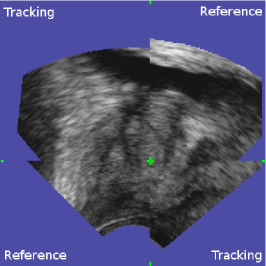

The first experiment evaluates the capacity of the kinematic probe movement model to estimate a probe position sufficiently close to its real position with respect to the gland. For this test, 786 registrations of the biopsy volumes of 47 patients were performed with the corresponding panorama volumes. The registrations were then visually validated either by the clinician immediately after biopsy acquisition or off-line by one of the authors. This was carried out using a volume viewer that allows to overlay and to explore the reference and the tracking volume after application of the registration transformation (see Fig. 13). Note that the accuracy of a large and randomly chosen subset of the registrations classified as valid was evaluated to 0.8±plus-or-minus\pm0.5 mm, cf. the accuracy study presented in Sec. 6.2, which indicates that only few registrations were falsely identified as correct. In this study, 769 (97.8%percent\%) volumes were classified as valid, and 17 (2.2%percent\%) were classified as failures. The 17 failures occurred with volumes that did not contain enough information about the prostate, i.e. the tracked object was literally ”out of view”. This was caused by inadequate US depth or probe pressure (prostate capsule not visible) in 11 cases, partial probe contact with the rectum in 1 case, extremely lateral volumes containing only a small part of the prostate in 4 cases and an incomplete panorama in 1 case. Note that the failures were not caused by patient movements.

Refer to caption

Figure 13: Viewer for visual validation. The viewer shows transverse (a), sagittal (b) and coronal cuts (c) simultaneously. The registration volumes are overlaid: the upper-left and lower-right corners of each view show the tracking volume, while the lower-left and upper-right corners show the reference volume. The green cut point is the 3D point where the three image planes intersect. The user can move the cut point freely in each view, allowing him to explore the entire volume (changing the point in one view changes the spatial position of the other two views).